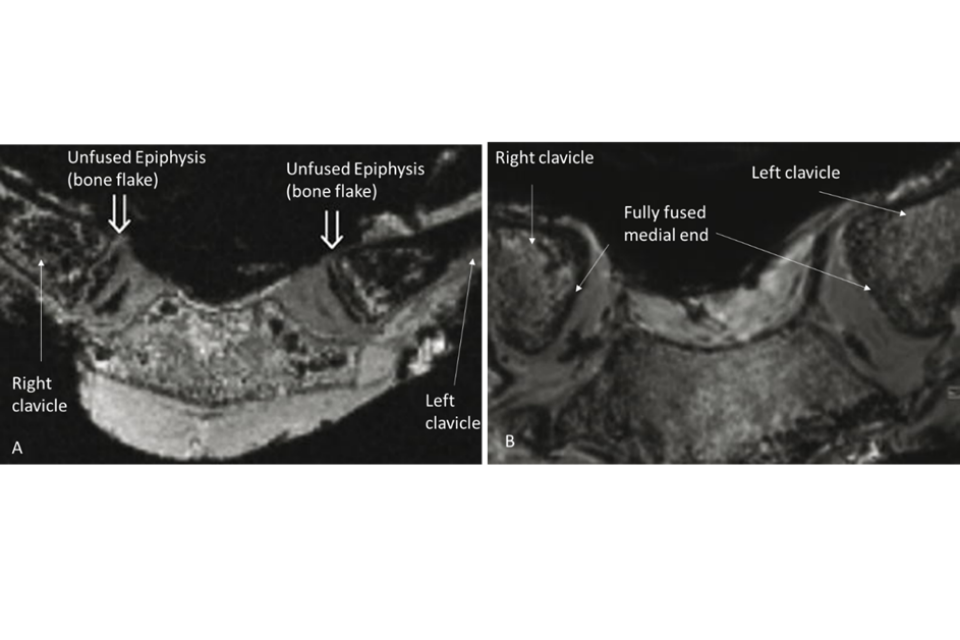

4.56. Age assessment using the clavicle focuses on the appearance and fusion of a thin flake of bone – the epiphysis, at the medial end of the shaft – to the remainder of the bone. The epiphysis appears and then fuses with the shaft of the bone throughout the late teenage period and into the early 20s (figure 8). The earliest that full maturity has been observed is at age 21 years for both females and males but for most individuals, fusion remains incomplete until age 25 (Ekizoglu et al., 2021; Hillewig et al., 2013; Schmidt et al., 2007, 2016, 2017; Vieth et al., 2014).

Figure 8: Two Magnetic Resonance images showing unfused epiphyses of the clavicle in a female aged 14.9 years (A) and fully fused medial ends of the clavicle in a male aged 36.3 years (B). (Images courtesy of Schmidt et al., 2007.)

MRI described above